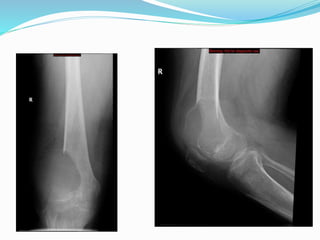

Case